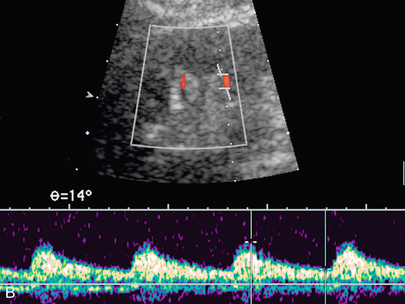

Еще одним критерием РАС является длительное время разгона более 0,07 секунды. Время ускорения – это временной интервал от начала систолы до раннего систолического пика. При притупленных формах сигналов этот ранний пик может отсутствовать, и измерение должно продолжаться от начала систолы до первой точки отклонения. Наличие морфологии волны тардус-парвус помогает в диагностике тяжелой формы РАС; однако его отсутствие не исключает РАС.Спектральная форма волны тардус-парвус определяется медленным подъемом вверх (тардус) и расширением спектра с притуплением систолического пика (парвус) ( рис. 9-15 ). Важно отметить, что у пациентов с атеросклеротическим заболеванием податливость сосудов может быть снижена, что делает морфологию волны тардус-парвус менее очевидной.

РИСУНОК 9-15. Стеноз почечной артерии. При дуплексной допплерографии сегментарной артерии нижнего полюса задержанное систолическое ускорение (тардус) и малая форма волны (парвус) соответствуют стенозу верхнего отдела, и необходима дальнейшая оценка главной почечной артерии, если стеноз еще не был непосредственно визуализирован.